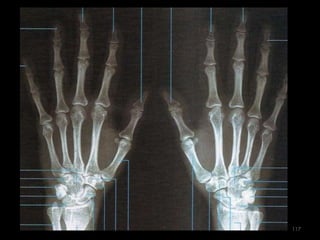

Incidência mãos e punhos para idade óssea115

116

117

Incidência PA Mão118

119

120